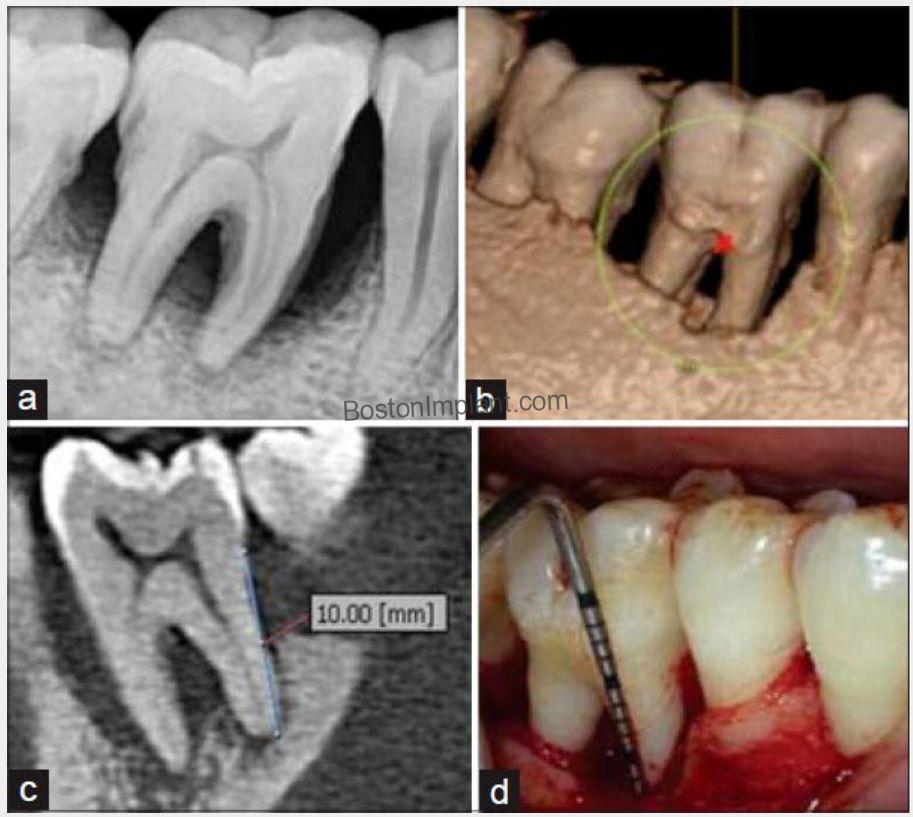

3. Periodontics (Gum Disease): Periodontitis, also known as gum disease, is a chronic inflammatory condition that damages the gums and bone supporting the teeth. Traditionally, diagnosis relied on tactile sensation, which could be uncomfortable for patients and wasn’t always accurate.

Thanks to CBCT, we can now diagnose gum disease easily and accurately.